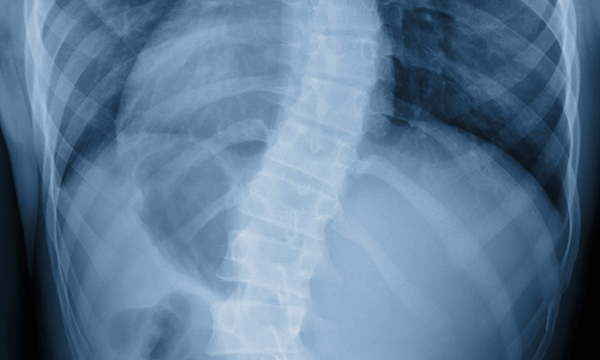

This is a summary of the peer-reviewed article: Abdominal X-rays in children: indications, proced